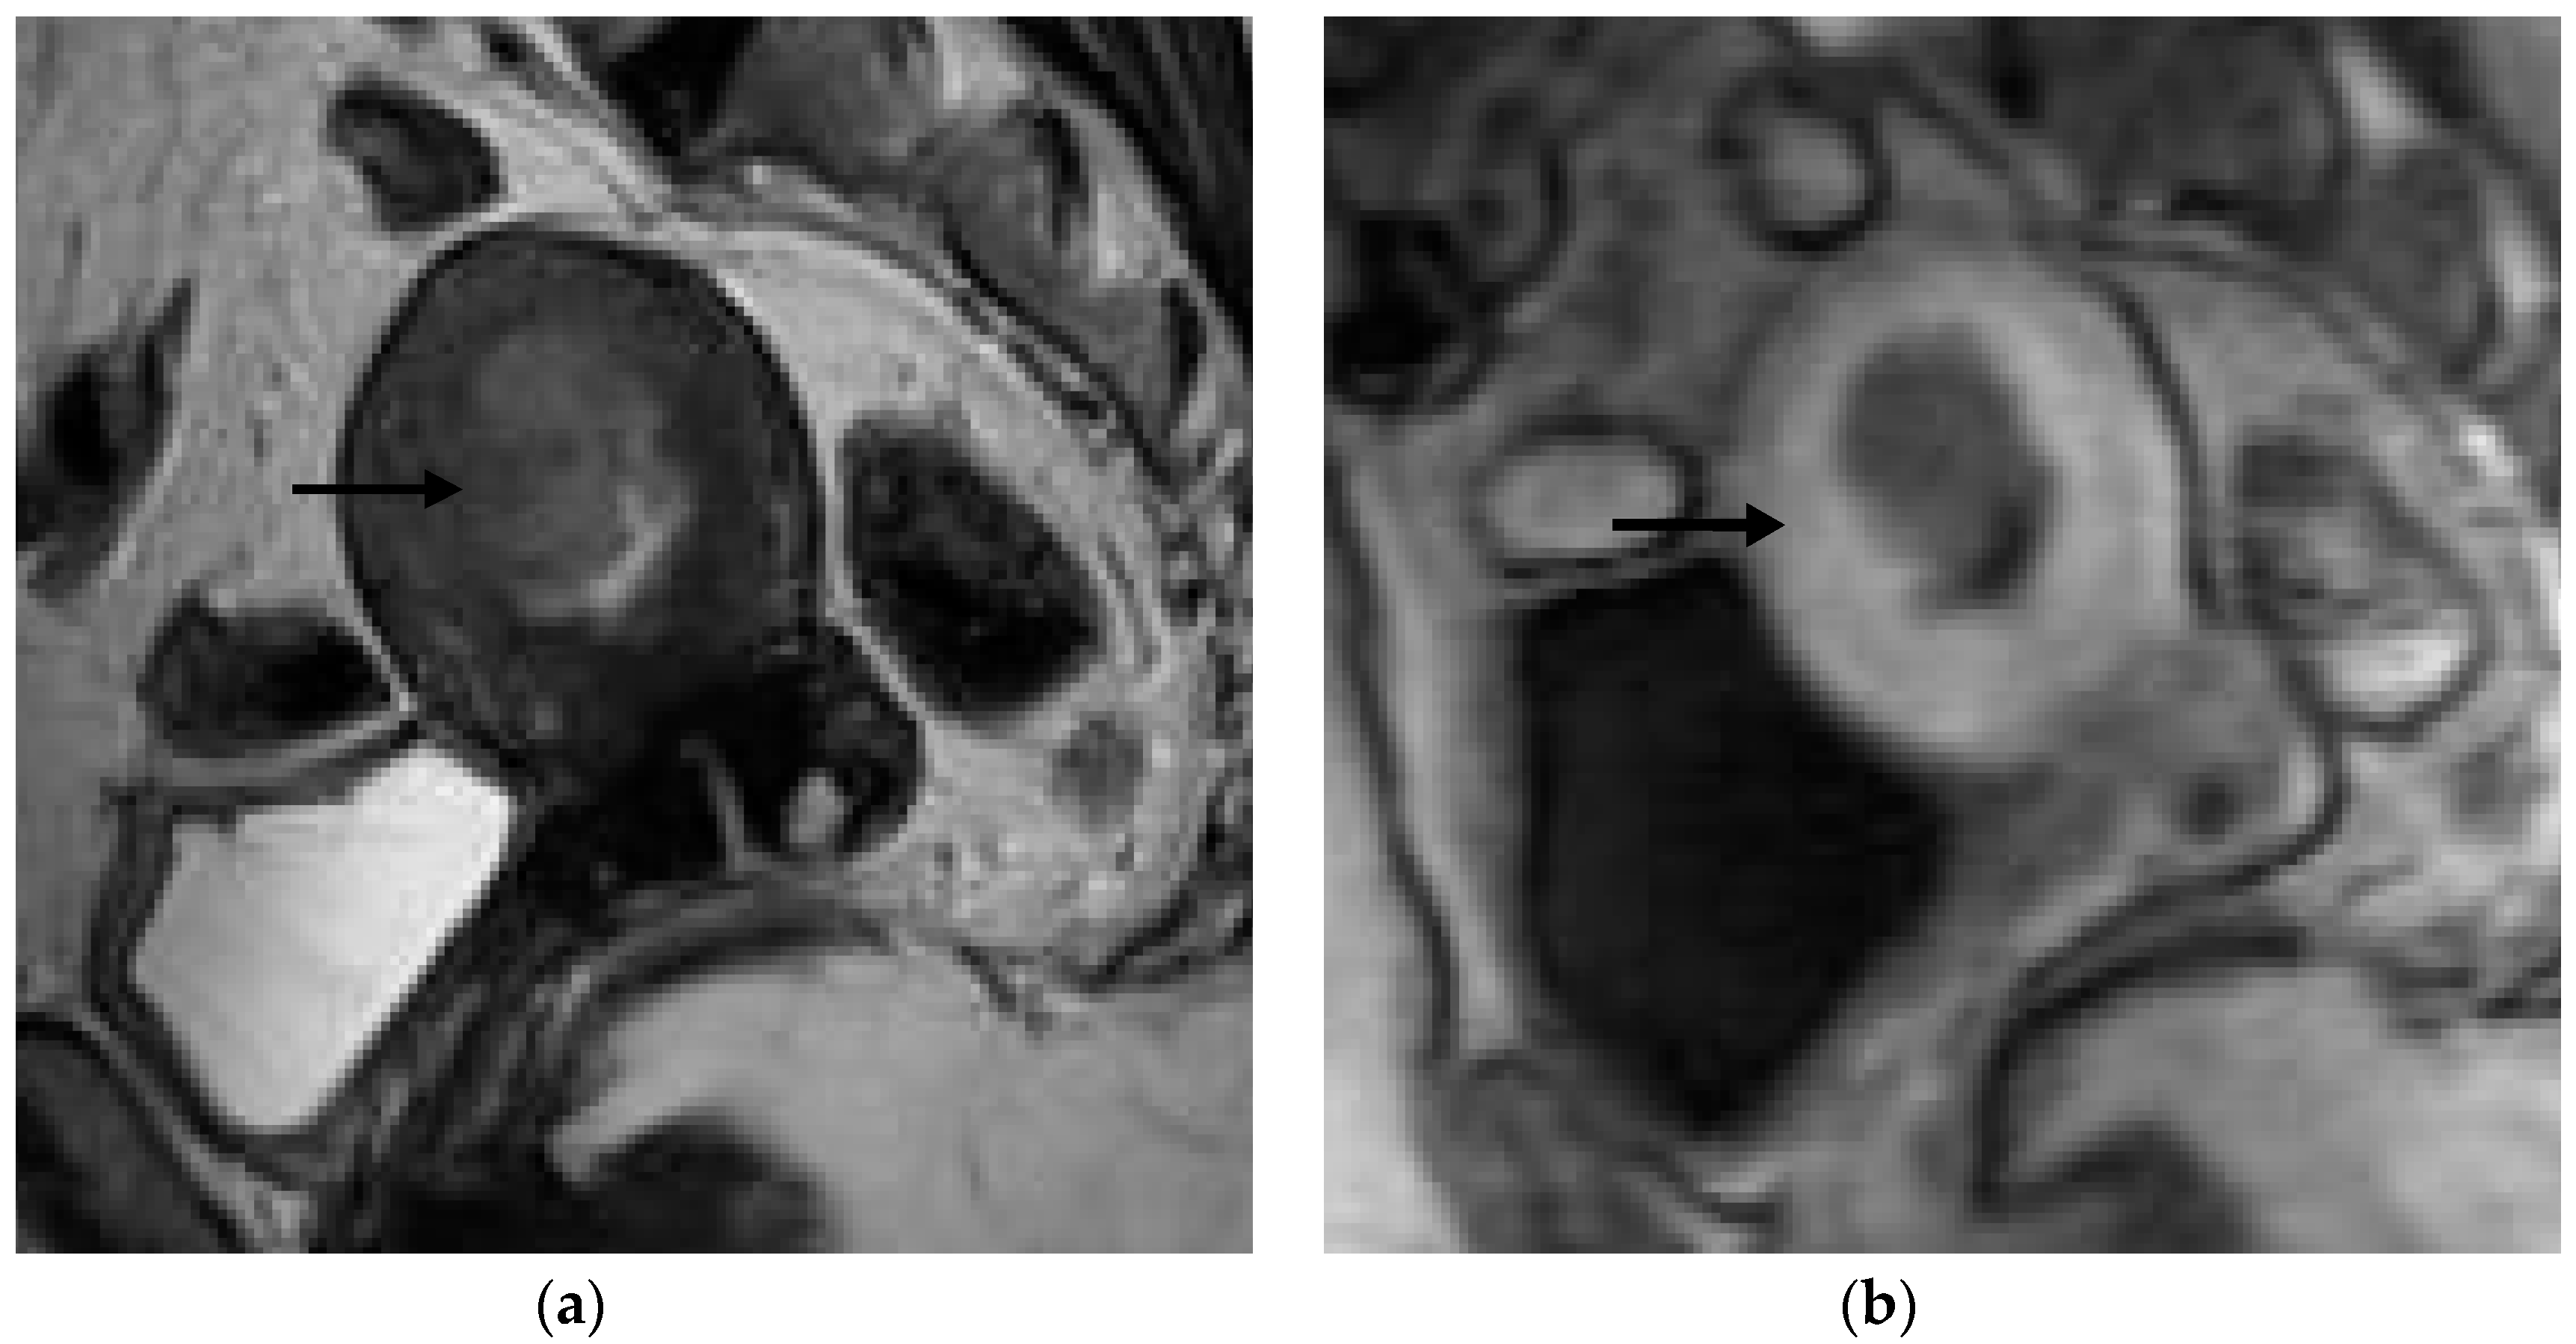

Figure 1, Figure 2, Figure 3 and Figure 4 depict the representative MRI images of tumors with < 50% myometrial invasion and ≥50% myometrial invasion, as well as the representative combined T2WI+DCE-MRI images for false-positive and false-negative cases, respectively. The diagnostic performance of MRI in predicting the depth of myometrial invasion is presented in Table 2 and Table 3. The depth of myometrial invasion (any depth) was correctly determined in 75% (n = 24) and 78% (n = 25) of cases on T2WI and DCE-MRI alone, respectively, whereas the percentage increased to 91% (n = 29) of cases when the T2W images were read together with those obtained by DCE-MRI.

Figure 3. Representative MRI images of endometrial carcinoma of a false-negative case in a 50-year-old postmenopausal woman. (a) Sagittal T2WI MRI image shows a hyperintense lesion with blurring of the junctional zone (arrow). (b) DCE-MRI image shows a hypointense lesion with irregularity of the subendometrial enhancement (arrow) and <50% myometrial invasion. However, the histopathological result revealed ≥50% myometrial invasion.